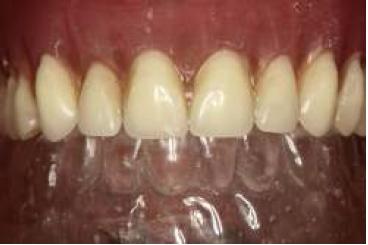

Paciente de sexo femenino, de 72 años de edad al momento del procedimiento. Desdentada total superior e inferior, portadora de prótesis removible total acrílica superior en mal estado. Consulta por la posibilidad de rehabilitar por medio de implantes la zona mandibular (fig. 1), ya que las prótesis convencionales realizadas hasta ese momento carecen de estabilidad. Dentro de la anamnesis la paciente relata estar en tratamiento con medicamentos para la hipertensión.